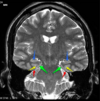

Which part of the brainstem is this? [1]

Label A & B [2]

Pons

A: 4th ventricle

B: Pons